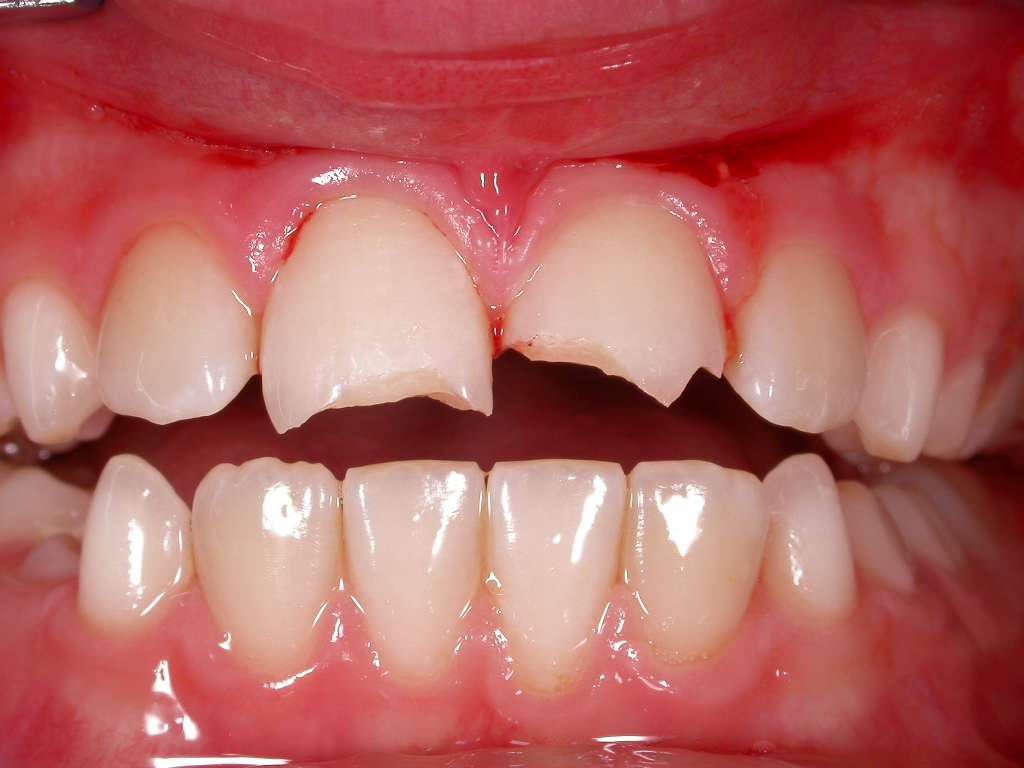

Frontzahnfrakturen nach Unfall

Vorher: Frontzahnfrakturen nach Unfall

Rekonstruktion mit vollkeramischen Kronen

Nachher: Rekonstruktion mit vollkeramischen Kronen